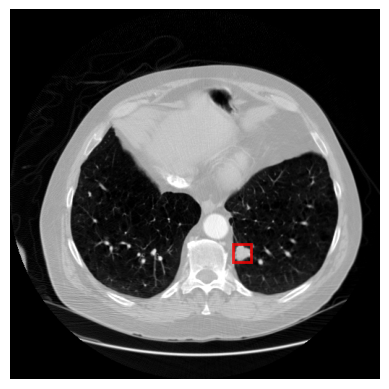

LUNA16

LUNA16 (Setio et al., 2017) is a public chest CT dataset for lung nodule detection, containing 888 3D chest CT scans with annotated nodule locations. We selected this dataset because it exemplifies key characteristics of medical imaging (Figure 5): (1) high resolution (typically 512 x 512 pixels per slice), necessary for capturing fine details; (2) small objects of interest, as nodules are subtle and occupy only a small portion of each scan; and (3) class imbalance, as nodules are relatively rare. Each nodule is annotated in 3D with a center point and diameter. To convert them into 2D bounding boxes, we identify the slices intersecting each nodule along the z-coordinate and project the center point to 2D coordinates on each slice. Using the diameter, we define a 2D bounding box around this point, allowing slice-by-slice nodule detection. Since DETR is designed for 2D object detection, we treat each 2D slice as an independent input to the model, enabling nodule detection in each slice separately. The dataset is randomly split for training (666 scans, 75%), validation (88 scans, 10%), and test (134 scans, 15%).